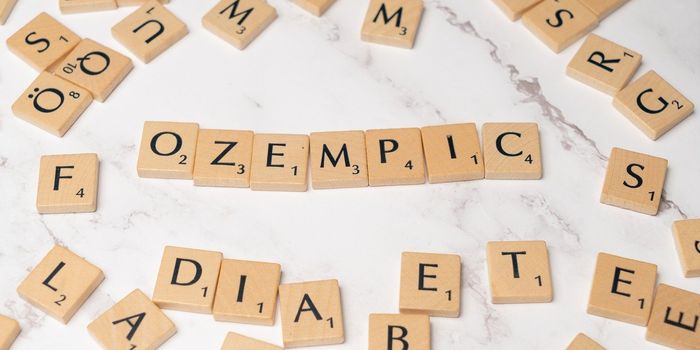

FEB 06, 2025ImmunologyA majority of patients with diabetes have type 2 diabetes. Specifically, more than 38 million Americans have diabetes an ...

JAN 28, 2025ImmunologyOzempic being a household name, GLP-1 receptor agonists (GLP-1RAs), a class of medications have garnered significant att ...